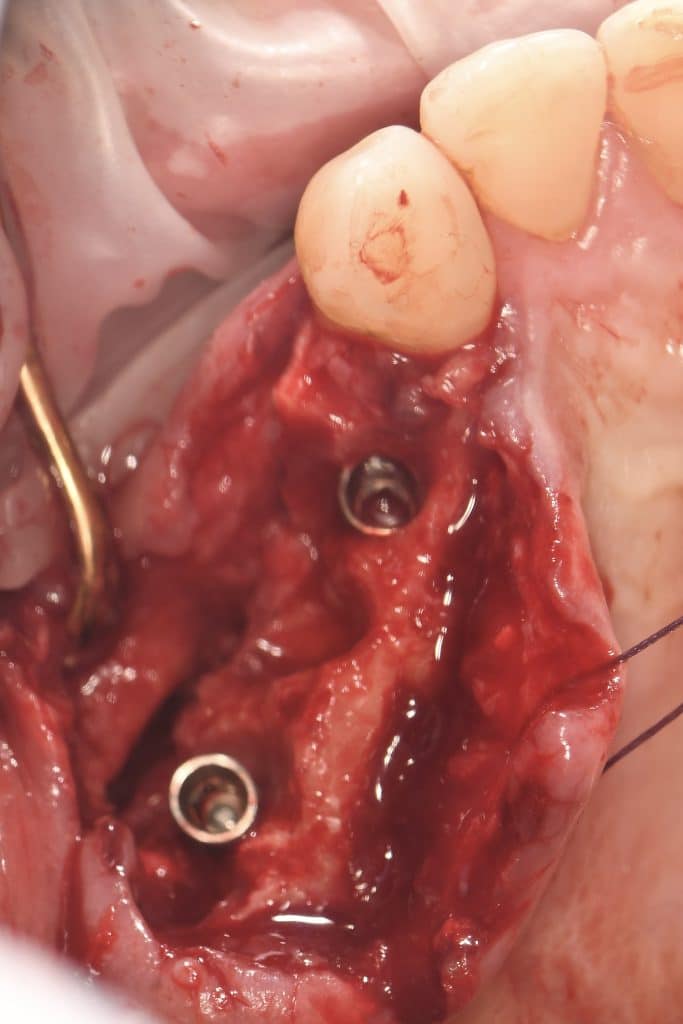

Case of the day where i extracted the 34-35-36 and an immediate placement of 2 implants in the 34-36 sites

sticky bone grafting GTO by osteobiol was used with straumann xenograft

Now healing in